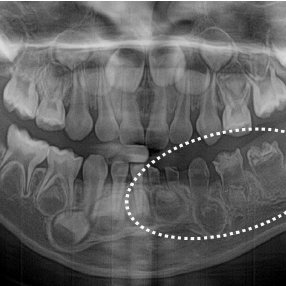

Regional odontodysplasia